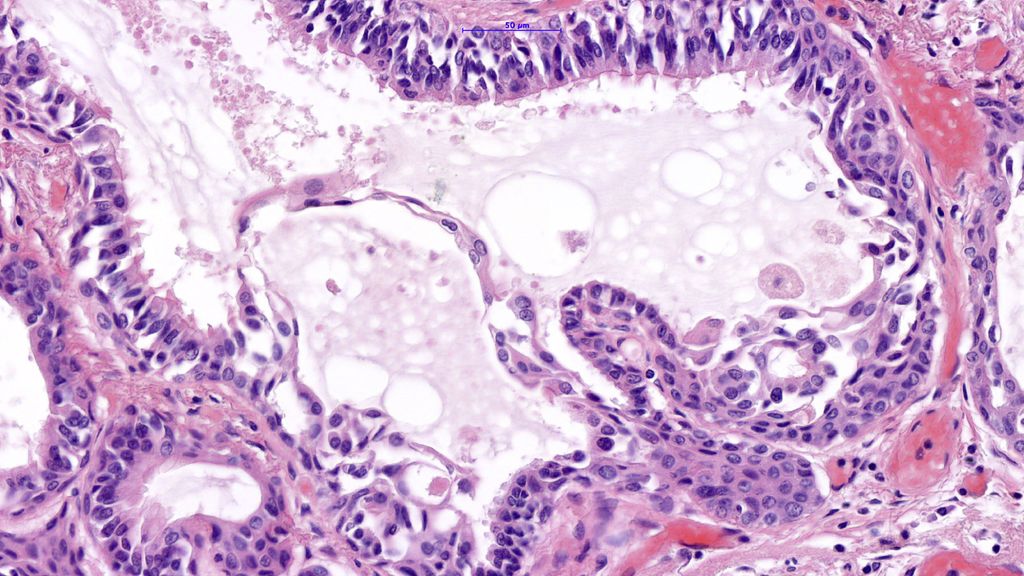

Abb. 3:Übersicht mit plattenepithelial differenzierten Zellen (oben) und Schleimproduktion/Freisetzung in der unteren Hälfte. Maßstab 200µm

Der ziliäre papilläre mukonoduläre Tumor der Lunge ist eine neue Entität, der eine charakteristische Morphologie aufweist (Abb. 1–4). Aufgrund der bisherigen Berichte kann von einer geringen Malignität ausgegangen werden. Die molekularen Signaturen lassen aber die Möglichkeit einer Rezidivierung und eventuell sogar einer Metastasierung offen.Dementsprechend kann eine Prognose nicht mit Sicherheit abgegeben werden. Eine engmaschige Kontrolle in den ersten fünf Jahre nach Diagnose ist zu empfehlen.